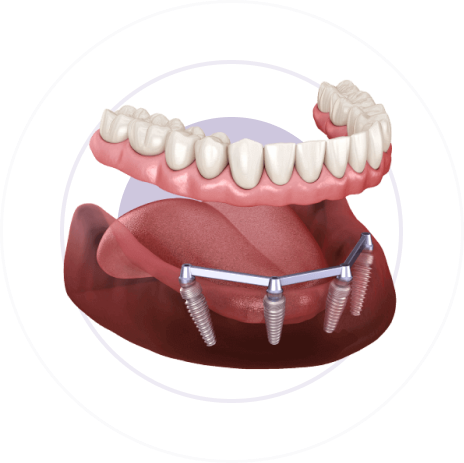

Имплантация All-on-4:

4 импланта + несъёмный протез за 1 день

В чём заключается технология All-on-4

Мы устанавливаем 4 импланта и несъёмный протез на всю челюсть за 1 приём

Всё просто: приходите к нам в клинику —

а через 5 часов выходите с готовыми зубами

Этап 3

Установим несъёмный протез на всю челюсть